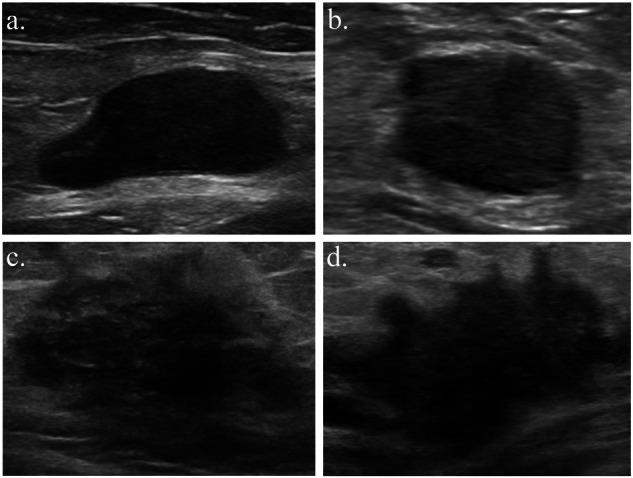

This study aimed to develop and validate a deep learning radiomics nomogram (DLRN) for the preoperative evaluation of axillary lymph node (ALN) metastasis status in patients with a newly diagnosed unifocal breast cancer. A total of 883 eligible patients with breast cancer who underwent preoperative breast and axillary ultrasound were retrospectively enrolled between April 1, 2016, and June 30, 2022. The training cohort comprised 621 patients from Hospital I; the external validation cohorts comprised 112, 87, and 63 patients from Hospitals II, III, and IV, respectively. A DLR signature was created based on the deep learning and handcrafted features, and the DLRN was then developed based on the signature and four independent clinical parameters. The DLRN exhibited good performance, yielding areas under the receiver operating characteristic curve (AUC) of 0.914, 0.929, and 0.952 in the three external validation cohorts, respectively. Decision curve and calibration curve analyses demonstrated the favorable clinical value and calibration of the nomogram. In addition, the DLRN outperformed five experienced radiologists in all cohorts. This has the potential to guide appropriate management of the axilla in patients with breast cancer, including avoiding overtreatment.

本研究旨在开发并验证一种深度学习影像组学列线图(DLRN),用于新诊断的单灶性乳腺癌患者腋窝淋巴结(ALN)转移状态的术前评估。2016年4月1日至2022年6月30日期间,对883例接受术前乳腺和腋窝超声检查的符合条件的乳腺癌患者进行了回顾性纳入。训练队列包括来自医院I的621例患者;外部验证队列分别包括来自医院II、III和IV的112例、87例和63例患者。基于深度学习和手工特征创建了DLR特征,然后基于该特征和四个独立的临床参数开发了DLRN。DLRN表现出良好的性能,在三个外部验证队列中,受试者操作特征曲线(AUC)下的面积分别为0.914、0.929和0.952。决策曲线和校准曲线分析证明了列线图具有良好的临床价值和校准性。此外,在所有队列中,DLRN的表现均优于五位经验丰富的放射科医生。这有可能指导乳腺癌患者腋窝的合理管理,包括避免过度治疗。